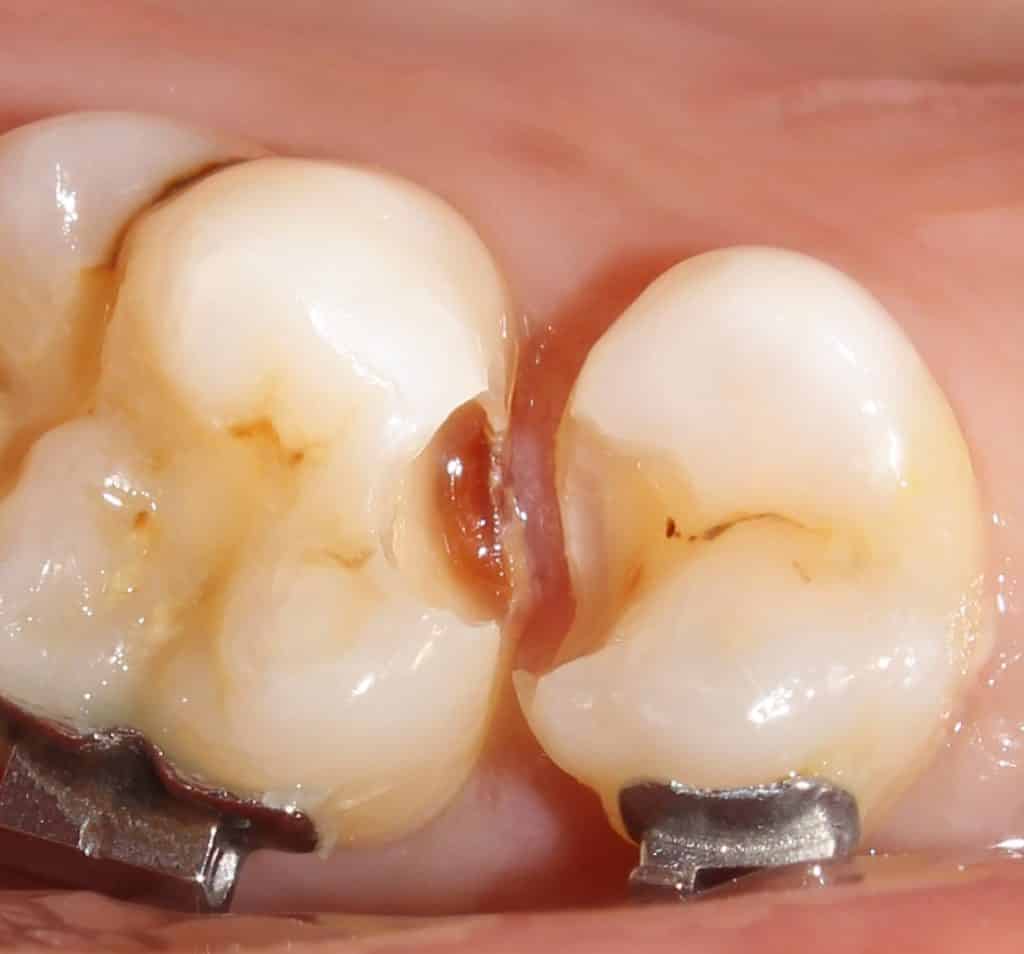

both preps are visualized.. the cervical margin of 15 is in enamel.. the margin of 16 is in dentin..